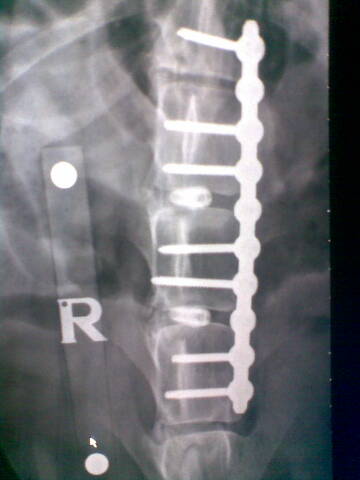

It was make or break. Noel said he could attempt something that had never been done before, the separating of discs from each other and the spinal chord via several screws inserted at a specific angle. These would give the spinal chord the room it needed to recover, or at least give it a better chance, although the procedure was a potentially a highly dangerous one and one that to Noel's knowledge had never been carried out before.

For those of you who are intrigued here's the actual miracle in place. Amazing, amazing people who do these things.

xray1.jpgxray2.jpg